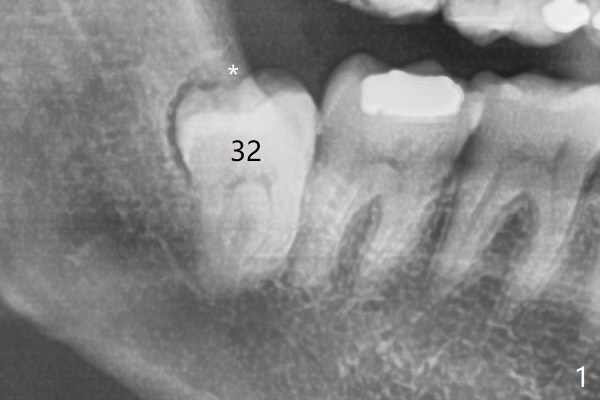

智齿牙龈出血       Last     Next

Xin Wei, DDS, PhD, MS 1st edition 06/07/2021, last revision 07/31/2021